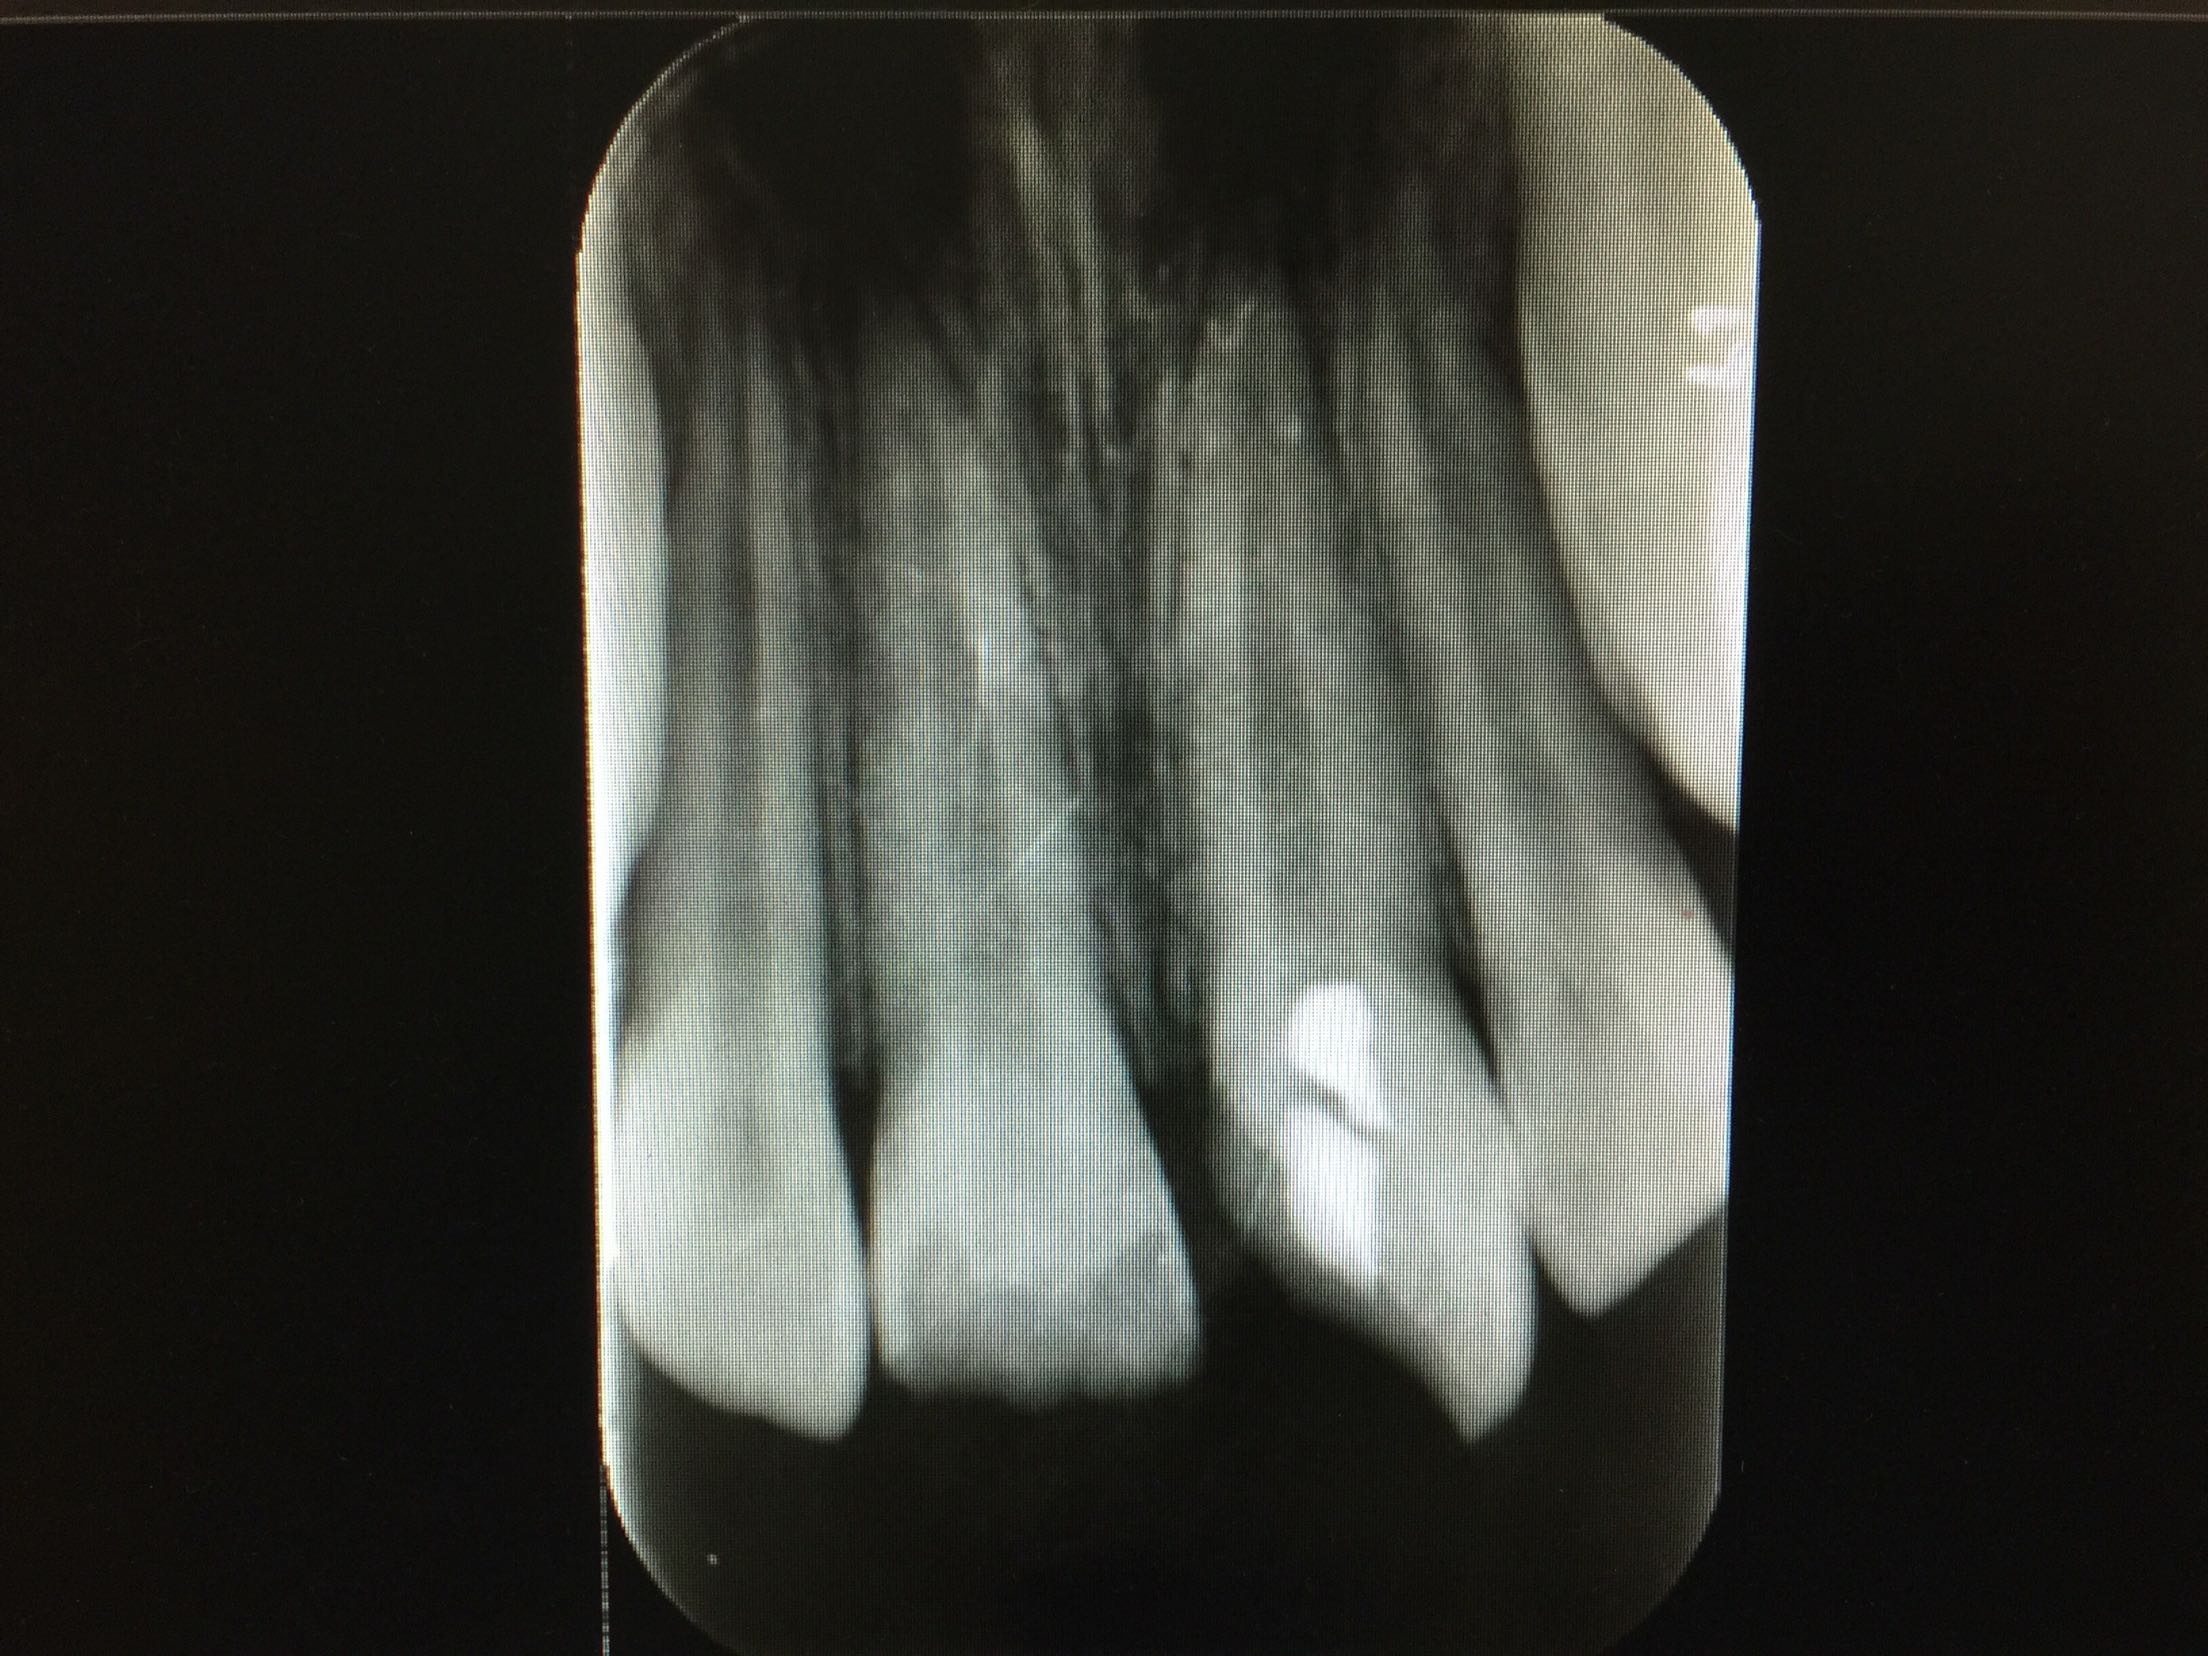

复诊,11,21牙进口玻璃离子垫底,前牙美容修复术调合,抛光。 3周后复诊:牙髓电活力测试11牙14,21牙15。 拍片:

11,21牙牙周膜腔未见明显增宽,很尖周无暗影。 建议继续拍片观察。 一月后复诊:牙髓电活力测试11牙13,21牙15。 拍片:11,21牙牙周膜腔未见明显增宽,很尖周无暗影。 建议11,21前牙树脂功能修复。 处置:行11牙,21牙牙树脂修复术。继续观察,约复诊。